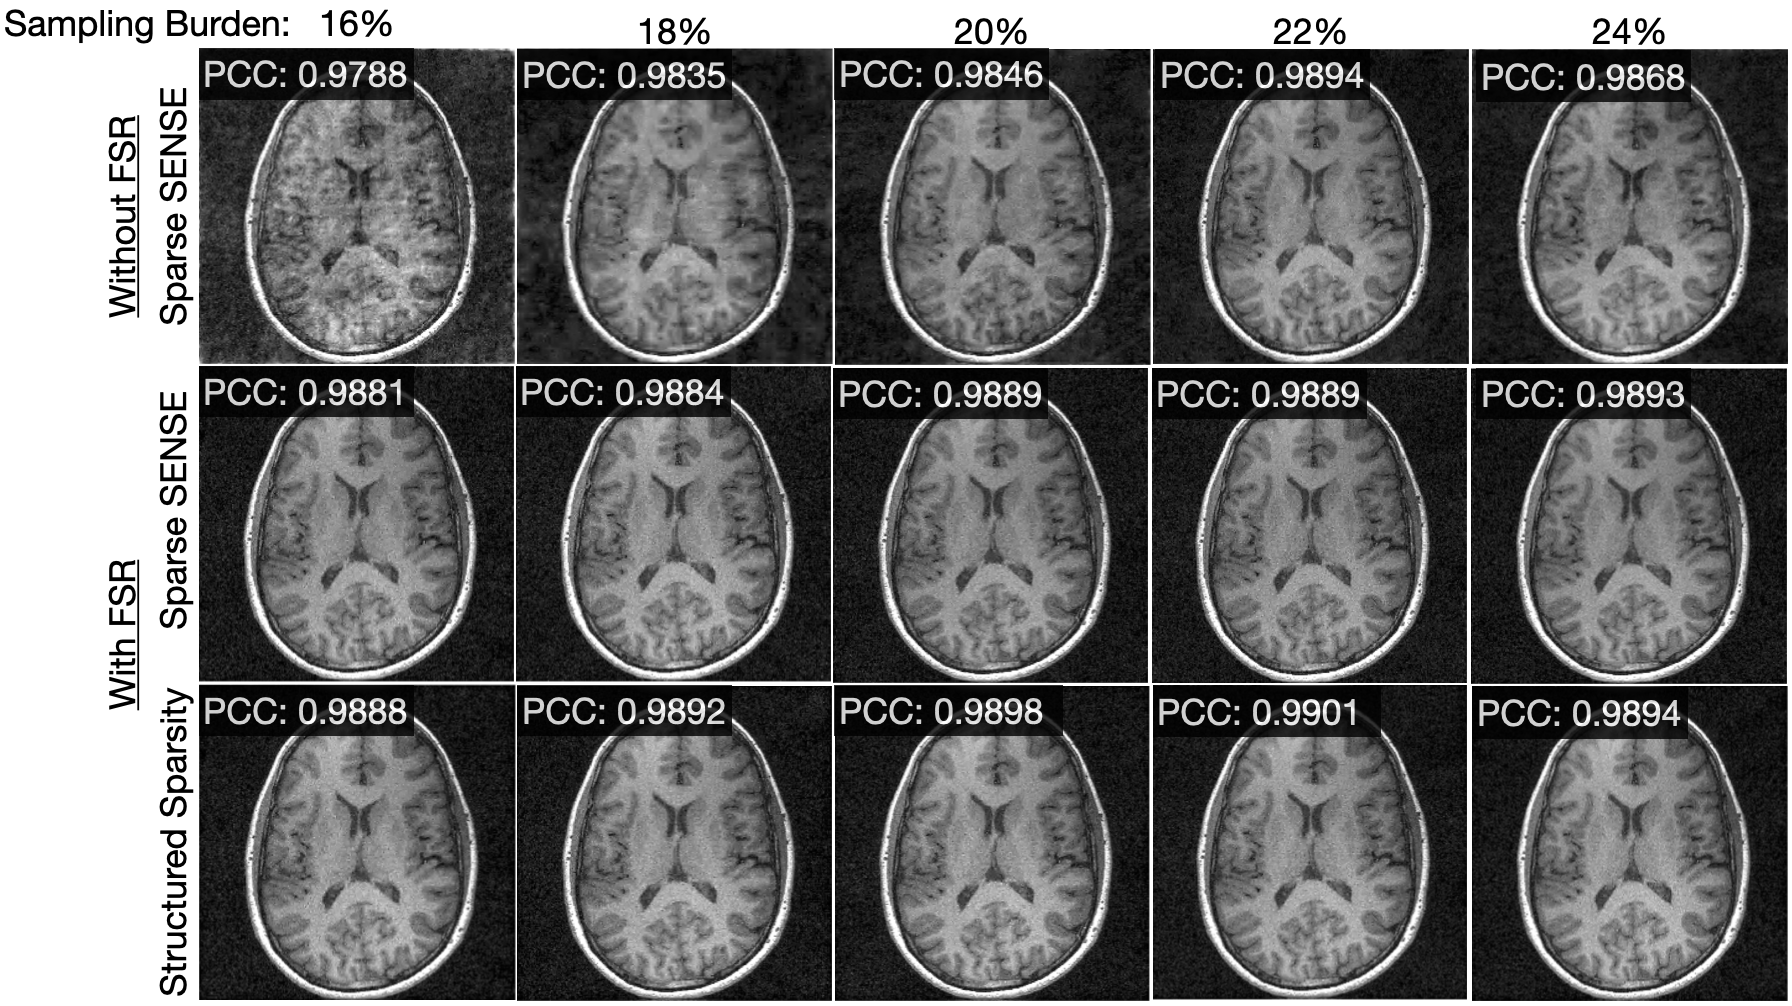

Figure 5 shows reconstructions for an axial slice of a brain for a variety of different sampling burdens using a sparsifying transformation comprised of wavelets and curvelets. In all cases, compressed sensing with structured sparsity outperforms Sparse SENSE. Note that compressed sensing with structured sparsity achieves a PCC of 0.98920.98920.98920.9892 with a sampling burden of 18%percent1818\%18 %, which is about what Sparse SENSE with the fully-sampled region achieves with a sampling burden of 24%percent2424\%24 %. This indicates that one can accelerate the MRI scan by an additional 25%percent2525\%25 % and achieve comparable or better image quality when taking advantage of structured sparsity.

Refer to caption

Figure 5: Reconstructions of an axial slice of a brain. For all sampling burdens, the PCC with structured sparsity is the highest.